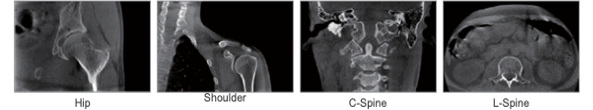

Өргөн диаметр ба офсет детекторын геометрийн шийдэл нь L-бүсийн нуруу, мөр, ташаа зэрэг биеийн олон төрлийн анатомийн хэсгийг скан хийх боломжийг олгодог.

Нуруу, толгой ба хүзүү, гар хөл, уушиг болон холбоосын (буглаа) судалгаанд зориулсан өндөр нарийвчлалтай конус цацрагт КТ